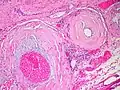

Amyloidosis, lymph node, H&E Amyloidosis, lymph node, polarizer

Amyloidosis, lymph node, polarizer

Micrograph showing amyloid deposition (red fluffy material) in the heart (cardiac amyloidosis). Congo red stain.

Micrograph showing amyloid deposition (red fluffy material) in the heart (cardiac amyloidosis). Congo red stain.